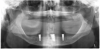

Six months after his last visit, the patient presented with complaints of unresolved pain in the lower gums and a referral from the denturist to assess the mandibular anterior region. The patient reported ongoing pain lasting more than 10 days without resolution despite repeated adjustments by the denturist to relieve areas of irritation. An area of ulceration was noted on the lingual gingiva of implant site No. 24, and a panoramic radiograph showed crestal peri-implant bone loss and thread exposure on all three implants (Figure 8), but this was unrelated to the observed lesion. Percussion of implant No. 24 and palpation of the buccal aspect did not yield a painful response. The tissue cuff surrounding the locator-type abutment was sensitive to palpation and localized to the lingual frenum adjacent to the implant.

Fig 7. Panoramic radiograph of implants following placement of locator-type attachments (3-month follow-up). Implants were well integrated with normal-appearing peri-implant bone.

Figure 7

Fig 8. Panoramic radiograph of implants at 6-month follow-up. Significant bone loss and thread exposure were noted around not only the affected implant No. 24 but all three implants.

Figure 8